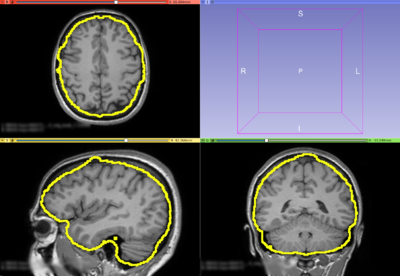

The Brain Volume Refinement (BVeR) extension is designed to assist neuroscience studies. The BVeR algorithm is suitable for a broad use of healthy brain structural MRI images, e.g. T1w and T2w, offering broad application in many large data analyses. The main contribution of the proposed method is related to the reduction of manual interference in the brain volume refinement after an automatic skull stripping procedure been performed, helping to reduce human errors and processing time. Even though the BVeR method does not provide a fully brain extraction algorithm, it can be helpful as a ad hoc image processing step in which increase the quality of well-known brain extraction algorithm in the literature. Any brain extracting frameworks can be refined with this method, e.g. FSL-BET, FreeSurfer, BEasT, 3DSkullStrip, ROBEX, OptiBET and many others.

- Structural T1w and T2w brain volume correction: BVeR

- Use Case 1: Cortical thickness surface delineation.

- When dealing with grey-matter overestimate due to badly brain extraction step.

- Use Case 2: Brain atrophy

- Assist in the total brain volume estimate also reducing the non-brain tissues belonging outside the grey-matter tissue frontier.